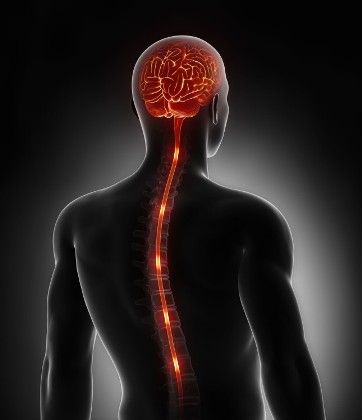

При спазмах часто призначають міорелаксанти. Якщо ж всі спроби виявилися марними, тоді доводиться проводити операцію, в ході неї лікар розсікає у спинному мозку ті нерви, які утворюють спастичні скорочення сечового міхура.

Зниження м’язового тонусу сечовивідного органу і неповний виведення рідини свідчать не тільки про патології малого тазу, але і про захворювання інших органів. Хвороби спинного мозку порушують виводить функцію сечового міхура. До них відносяться:

До захворювань ЦНС, при яких розвивається стан залишкової сечі в сечовому міхурі у чоловіків і жінок, відносяться мієліт, порушення функціонування спинного і головного мозку.

До останньої групи причин відносять втрату центральною нервовою системою контролю над сечовипусканням. В таких випадках сам міхур здоровий, а проблема криється в м’язах органу або сфінктера, які перестають скорочуватися в потрібний момент.

Причинами такого стану організму часто бувають склероз, травми спинного і головного мозку, вроджені патології ЦНС, також хвороби хребта. Справа в тому, що антидепресанти, антиаритмічні, сечогінні, гормональні препарати, ліки від хвороби Паркінсона, а також деякі знеболюючі негативно впливають на тонус органу.